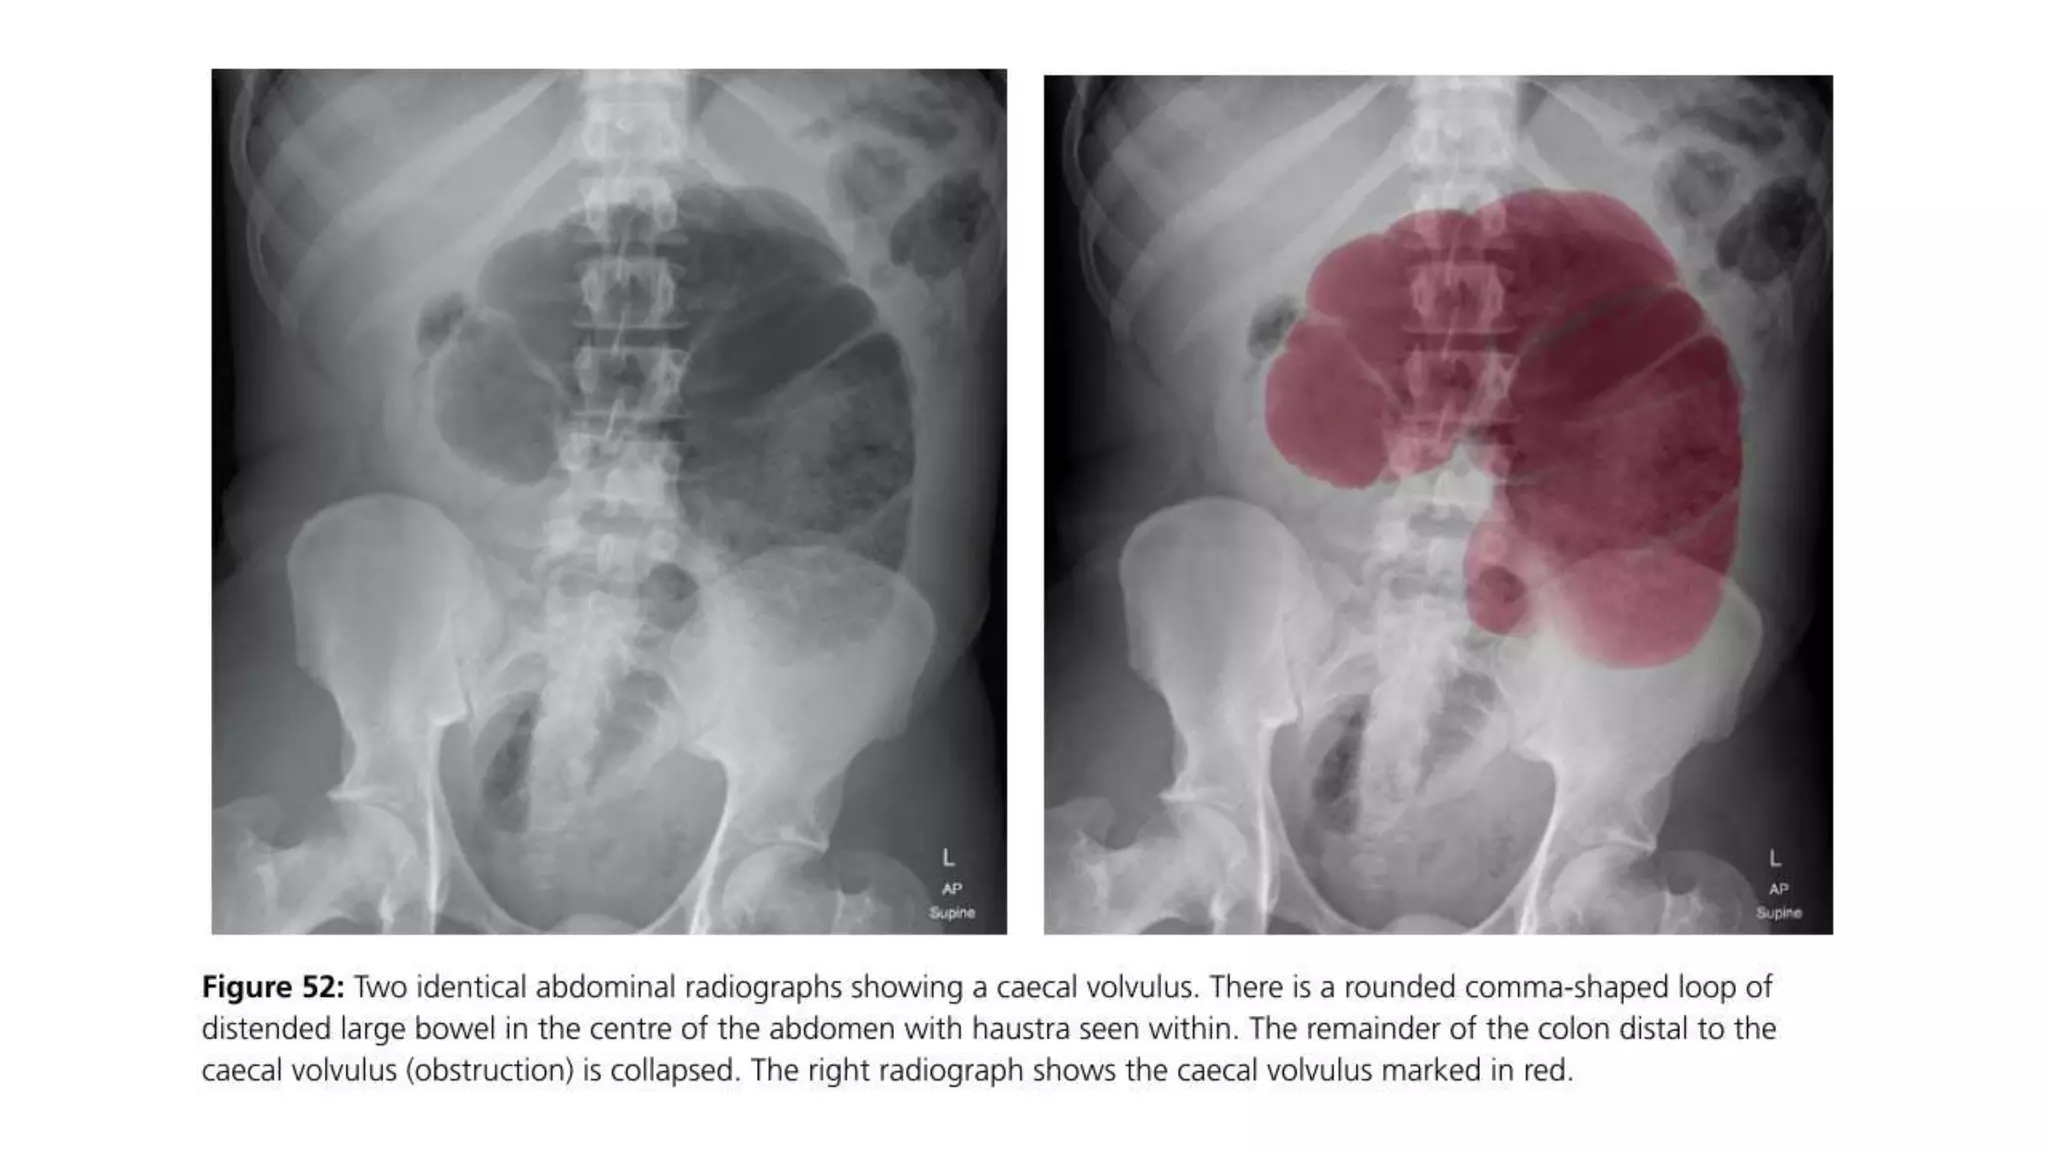

• CT scan — In patients with axial torsion of the cecum (type I or II), a

computed tomography (CT) finding of the "whirl sign" (twisting of the

mesentery around the ileocolic vessels) is pathognomonic for cecal

volvulus. In addition, CT scan may also demonstrate signs of bowel

obstruction (a massively dilated cecum with associated small bowel

dilation) (image 5) or signs of colonic or small bowel ischemia (mural

thickening or mesenteric edema) [9]. In patients with a cecal bascule (type

III), CT scan shows the cecum folding upward, resulting in obstruction

without the axial twist of the mesentery (image 6).

MANAGEMENT

• The management for patients with a cecal volvulus is primarily

surgical. Nonoperative reduction of cecal volvulus (eg, by

colonoscopy or barium enema) is rarely successful (<5 percent) and

could cause perforation; it therefore should not be attempted.

• In addition, colonic necrosis may be missed in 20 to 25 percent of

patients who undergo nonoperative reduction, and such patients may

develop colonic perforation [2,14,30-32].

• Surgical approaches to cecal volvulus vary depending upon

intraoperative findings and patient stability